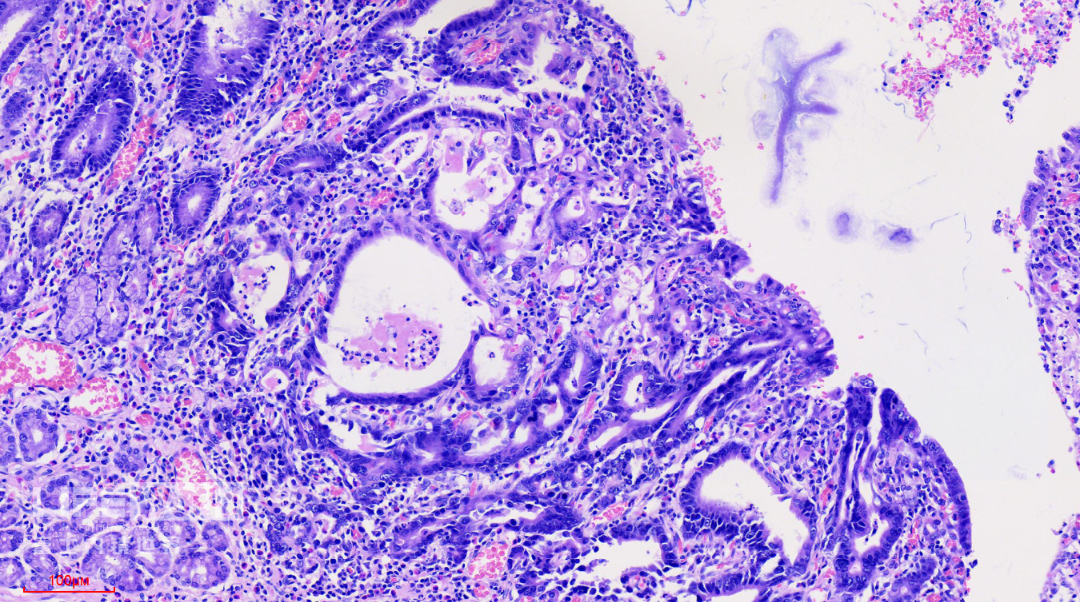

HE染色:2号切片示中分化腺癌,6号切片示高级别上皮内瘤变,局灶癌变。

这是2号切片,病变位于一条皱襞顶端。

病变处(红圈内)可见不规则的腺管状结构,部分呈筛网状。图中可以看出,病灶间可见相对正常的胃底腺结构。图片中最深的病灶已经侵及粘膜肌层。

病变处细胞异型性明显。病变内部可见多处扩张的腺管,内部可见坏死碎片。对应胃镜图片上的白色球状物。

此为病变最深的地方,癌变的腺管侵及粘膜肌层。

CK-pan染色显示肿瘤细胞为上皮细胞,呈不规则腺管状排列,提示为中分化腺癌。

SMA染色:粘膜肌层完整,肿瘤细胞侵及粘膜肌层,但未突破。